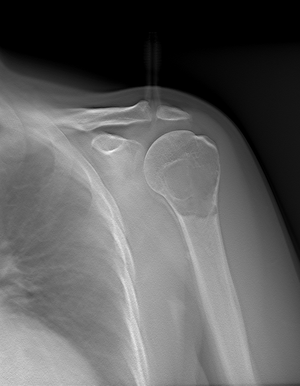

Рентген диагностика заболеваний опорно-двигательного аппарата

Рентгенография костей